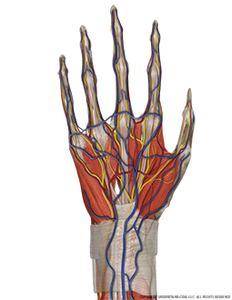

Hand and Wrist Complete Palmar Image

- Regular price

- $125

- Sale price

- $125 Sale